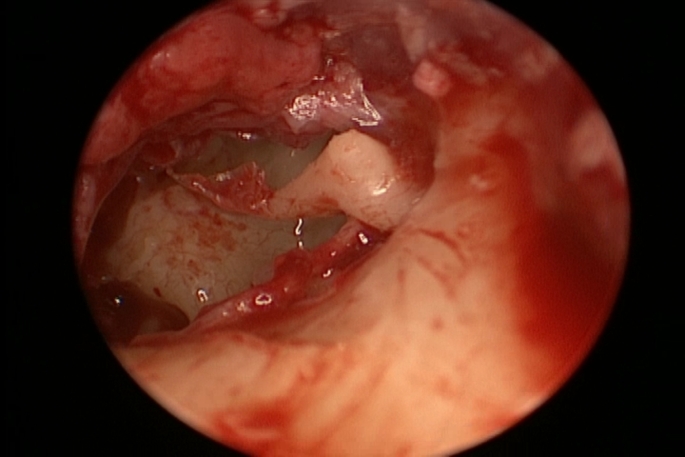

Objective: Endoscopic ear surgery (EES) is engaged nearly in all otology procedures in this era. The widespread application is faced by raised drawbacks that EES can induce thermal injury to the inner ear structures.

Methods: This retrospective study investigates the effect of endoscopic tympanoplasty on the postoperative sensorineural element of hearing and other inner ear functions. Cases of endoscopic tympanoplasty admitted to the tertiary referral center in the period of the study were included. Important audiologic data were collected including the preoperative and postoperative bone conduction threshold and air bone gap. The total endoscopic usage time during surgery was collected. Appropriate statistical testing was performed using SPSS 20.